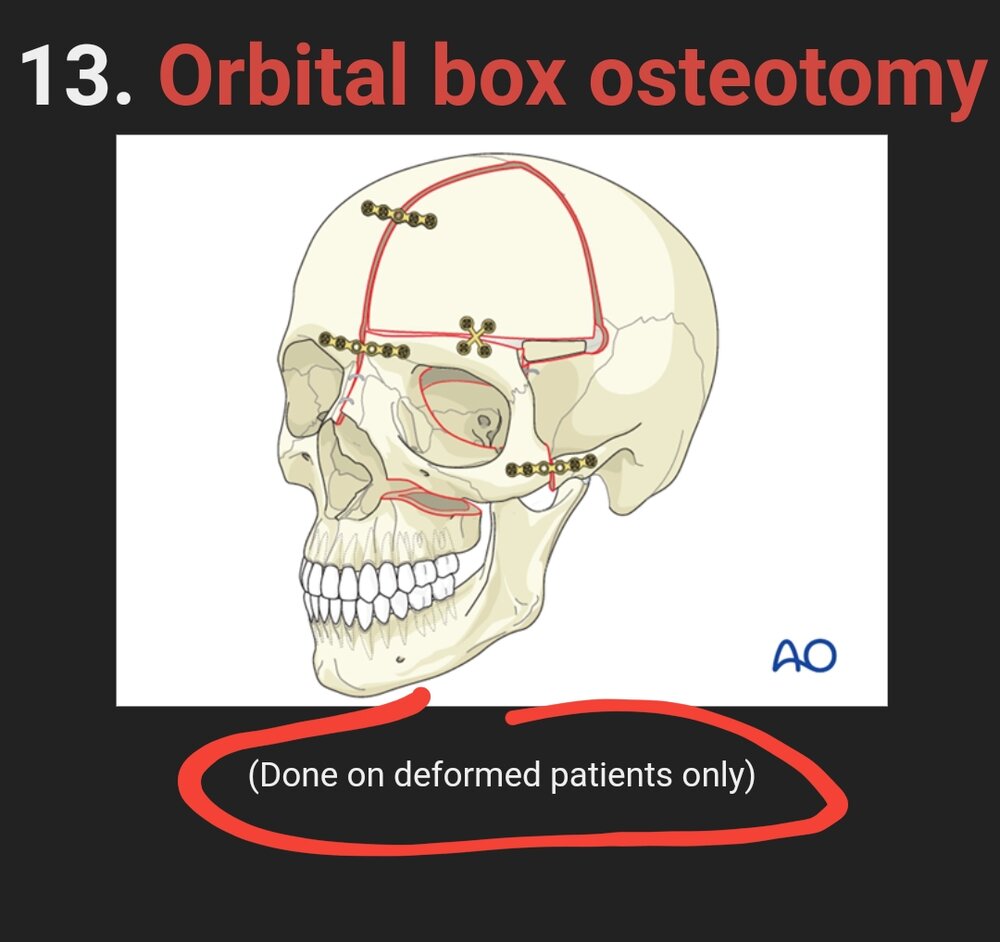

13. Orbital box osteotomy

(Done on deformed patients only)

13. Orbital box osteotomy

(Done on deformed patients only)